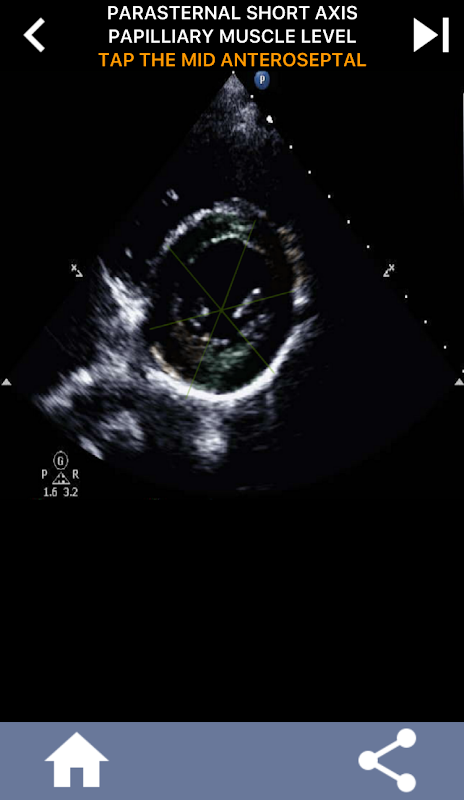

AHA kalp segmentlerini öğrenmek için sınava dayalı görsel yaklaşım: Ekokardiyografi

Bu uygulama, genellikle en iyi öğretim yöntemi olarak bulduğum gerçek yankı görüntülerini kullanarak bilginizi test edecek.